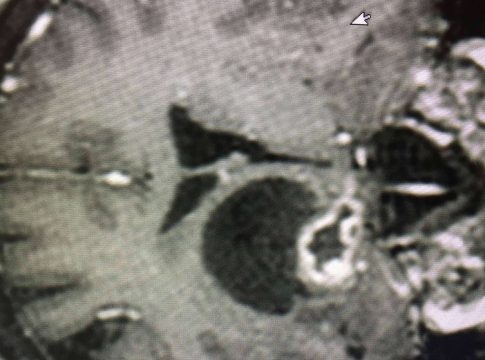

Según los especialistas, la resección tumoral es un tipo de proceso similar a la biopsia cerebral, con la diferencia de que busca eliminar el tejido tumoral presente en el resto del tejido cerebral. Sin embargo, no todos los diagnósticos de tumores cerebrales se resuelven con una resección tumoral, debido a que existen masas difíciles de diferenciar.

El tumor cerebral más frecuente en adultos es la metástasis, un foco tumoral procedente de un tumor maligno en otro órgano a distancia, y cuyas células han llegado al cerebro por intermedio de la sangre. En función del tipo de metástasis, su extensión, su localización y el factor de riesgo, el mejor tratamiento puede ser una resección cerebral.

Algunos de los tumores primarios más perjudiciales son los gliomas o astrocitomas, los oligodendrogliomas, los ependimomas, los subependimomas y sus variantes, los neurinomas. En ese caso, lo ideal es recurrir a una resección macroscópica completa, debido a que los tumores tienen células malignas aisladas en focos microscópicos a poca distancia del cuerpo del tumor.